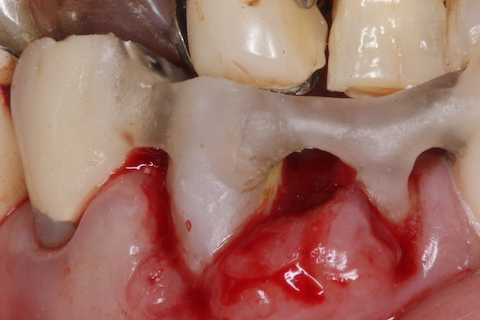

前回 ​のつづきで、再植と化粧をする。さすがに歯なしでは寂しい。

普通にズブズブと抜歯窩に再建した歯根を挿入する。

あとは接着固定しながら、歯冠を再建していく。